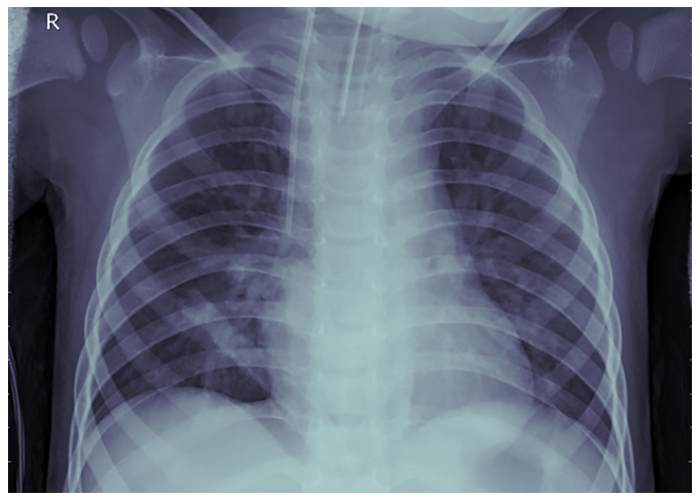

Fig. 4. Radiografie pulmonară - Pneumonie - PAUL MOONEY, 2018 (Chest X-Ray Images (Pneumonia) | Kaggle )

Acesta este locul unde Machine Learning poate fi de ajutor, prin automatizarea procedurii de diagnosticare, care necesită mult timp. În acest exemplu, am folosit librăria TensorFlow împreună cu un model pe TensorHub și setul de date de radiografii toracice de la Kaggle (Fig. 4 este a unui pacient sănătos, iar Fig. 5 este a unui pacient cu pneumonie). Pentru ochiul neexperimentat și chiar pentru cel al unui medic experimentat, acestea ar părea poate greu de distins, ceea ce este de înțeles. Să ne amintim că un medic dedică cea mai mare parte a timpului diagnosticării pacientului și dacă încercăm să distingem cele două scanări putem înțelege de ce.